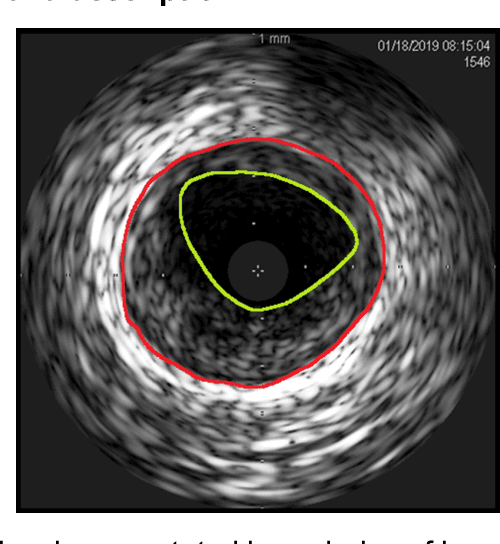

Abstract:Intravascular ultrasound (IVUS) imaging allows direct visualization of the coronary vessel wall and is suitable for the assessment of atherosclerosis and the degree of stenosis. Accurate segmentation and measurements of lumen and median-adventitia (MA) from IVUS are essential for such a successful clinical evaluation. However, current segmentation relies on manual operations, which is time-consuming and user-dependent. In this paper, we aim to develop a deep learning-based method using an encoder-decoder deep architecture to automatically extract both lumen and MA border. Our method named IVUS-U-Net++ is an extension of the well-known U-Net++ model. More specifically, a feature pyramid network was added to the U-Net++ model, enabling the utilization of feature maps at different scales. As a result, the accuracy of the probability map and subsequent segmentation have been improved We collected 1746 IVUS images from 18 patients in this study. The whole dataset was split into a training dataset (1572 images) for the 10-fold cross-validation and a test dataset (174 images) for evaluating the performance of models. Our IVUS-U-Net++ segmentation model achieved a Jaccard measure (JM) of 0.9412, a Hausdorff distance (HD) of 0.0639 mm for the lumen border, and a JM of 0.9509, an HD of 0.0867 mm for the MA border, respectively. Moreover, the Pearson correlation and Bland-Altman analyses were performed to evaluate the correlations of 12 clinical parameters measured from our segmentation results and the ground truth, and automatic measurements agreed well with those from the ground truth (all Ps<0.01). In conclusion, our preliminary results demonstrate that the proposed IVUS-U-Net++ model has great promise for clinical use.